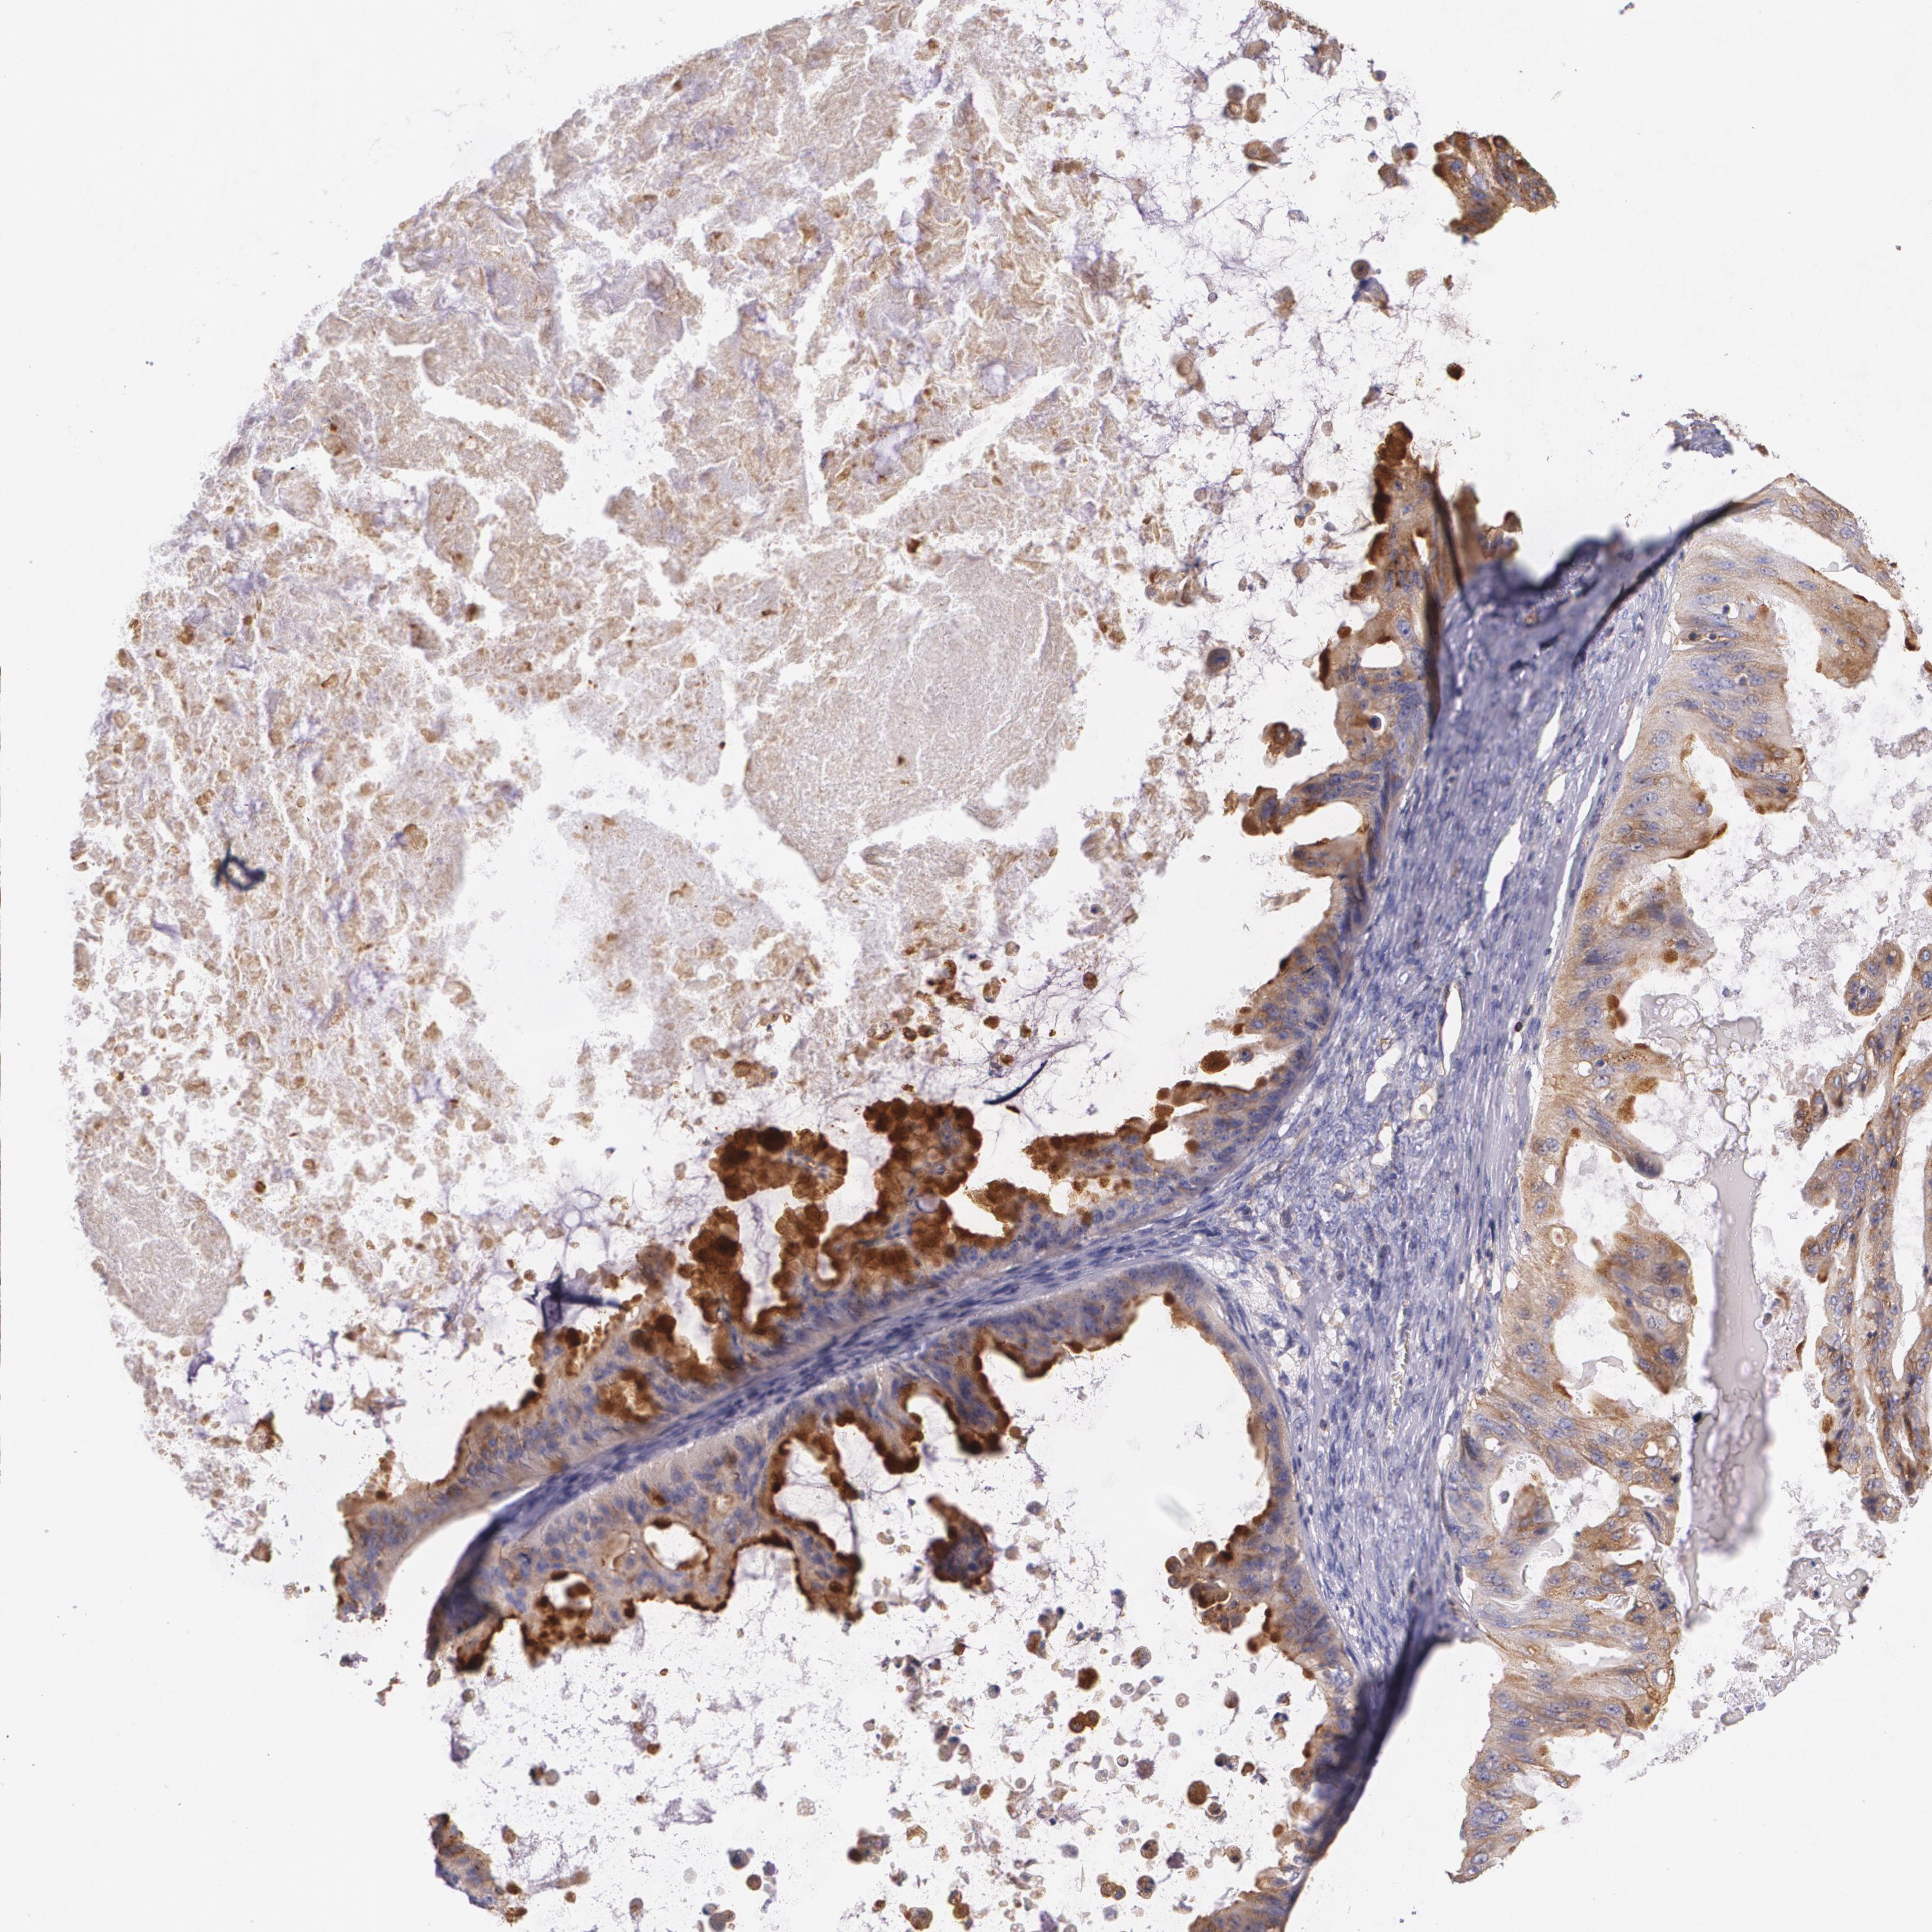

OVARIAN CANCER - Protein expressioni

A mouse-over function shows sample information and annotation data. Click on an image to view it in a full screen mode. Samples can be filtered based on level of antibody staining by selecting one or several of the following categories: high, medium, low and not detected. The assay and annotation is described here.

Note that samples used for immunohistochemistry by the Human Protein Atlas do not correspond to samples in the TCGA dataset.

Antibody stainingi

Antibody staining in the annotated cell types in the current human tissue is reported as not detected, low, medium, or high, based on conventional immunohistochemistry profiling in selected tissues. This score is based on the combination of the staining intensity and fraction of stained cells.

Each image is clickable and will lead to virtual microscopy that enables deeper exploration of all samples and also displays staining intensity scores, fraction scores and subcellular localization as well as patient and tissue information for each sample.

Antibody HPA006361

Antibody CAB002572

Staining

High

Medium

Low

Not detected

Intensity

Strong

Moderate

Weak

Negative

Quantity

>75%

75%-25%

<25%

None

Location

Nuclear

Cytoplasmic/membranous

Cytoplasmic/membranous,nuclear

Cystadenocarcinoma, serous, NOS

Carcinoma, endometroid

Carcinoma, NOS

Cystadenocarcinoma, mucinous, NOS